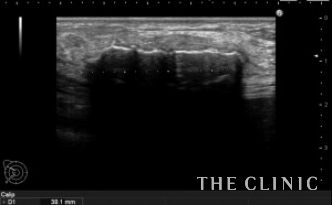

エコー所見です。

しこりを崩したためか、石灰化したカプセルが扁平に見えます。